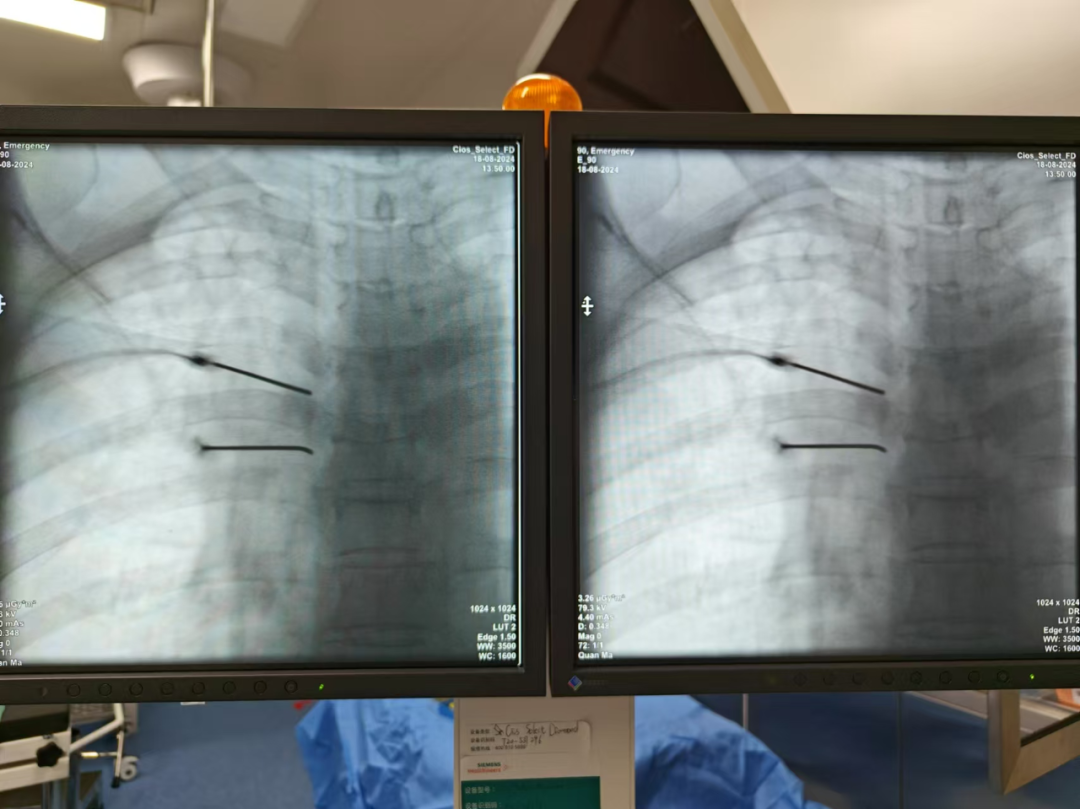

在親友推薦下,他們選擇來到酒泉市中醫(yī)醫(yī)院泌尿外科、普外二科、疼痛科接受治療。入院后,黨慶宏團(tuán)隊(duì)立即對彭奶奶病情進(jìn)行了全面評估,疼痛VAS評分9分,持續(xù)發(fā)作,老人沒有一刻安寧。疼痛科選擇為彭奶奶進(jìn)行周圍神經(jīng)阻滯鎮(zhèn)痛治療,為了從根本上解決問題,疼痛科為老人制訂了個(gè)性化鎮(zhèn)痛方案:電針穴位針刺止痛+周圍神經(jīng)射頻消融術(shù)。通過精心準(zhǔn)備和精準(zhǔn)治療,老人自訴疼痛明顯減輕,發(fā)作頻率大大減少,可以正常穿衣及活動。疼痛VAS評分3分,久違的笑容終于在老人的臉上綻放!

周圍神經(jīng)射頻消融術(shù)是一種微創(chuàng)手術(shù),通過精準(zhǔn)定位引起疼痛的周圍神經(jīng),利用射頻電流產(chǎn)生的熱量對神經(jīng)進(jìn)行調(diào)節(jié)或毀損,從而有效阻斷疼痛信號的傳遞,達(dá)到長期緩解疼痛的目的。

1.精準(zhǔn)治療:采用先進(jìn)的影像引導(dǎo)技術(shù),確保手術(shù)的準(zhǔn)確性和安全性,只針對病變神經(jīng)進(jìn)行處理,最大限度地保護(hù)正常組織。